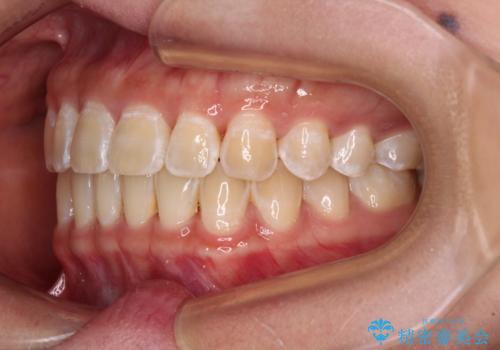

前歯の隙間と上下正中のズレを解消

- 上下前歯隙間と正中のズレを改善したいとのことで来院された患者様です。

自己管理を減らしたいとのことで、ワイヤー装置による矯正治療を行うこととしました。

正中がなかなか合わずに、2年近くの治療期間を要しました。